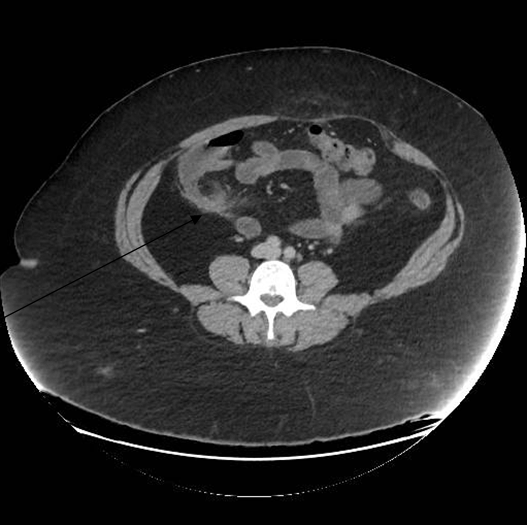

A 16-year-old girl presented with swelling in the right lobe of thyroid. There were no generalized symptoms like fever, malaise, night sweats and weight loss. There was no history of difficulty in deglutition or voice change. On clinical examination there was a single abscess of size 4x4 cm in right lobe of thyroid moving with deglutition. The margins were well demarcated, smooth surface, non-tender and overlying skin was normal with a tattoo mark on it (Figure 1). There were no clinical features of hypothyroidism or hyperthyroidism. Routine blood investigations were done; hemoglobin 11.0 g/dl, total leucocytes count 8600/mm3, neutrophils 67/mm3, lymphocytes 31/mm3 and eosinophils 2/mm3. The erythrocyte sedimentation rate was 20 mm. The Mountax test was highly positive more than 10 mm in diameter. Thyroid function tests T3, T4, TSH were normal. X-ray chest was normal. Ultrasonography of neck revealed a 50x45x20 mm solitary nodule in the right lobe of liver. This solitary thyroid nodule was showing thick irregular wall with central necrosis reported as suspected thyroid abscess. Magnetic resonance imaging scan of the neck showed a lesion of intermediate signal intensity due to presence of dense inflammatory cells and granulomas with central necrosis (Figure 2). A doubt about carcinoma of thyroid was placed as differential diagnosis. The CECT scan of neck was done to rule out carcinoma of thyroid gland. This was helpful in diagnosis of tubercular thyroid abscess as localized caseous lesion in right lobe of thyroid (Figure 3). Fine needle aspiration from this solitary thyroid nodule was done to confirm the diagnosis. The stained smears revealed degenerated and intact neutrophils, and macrophages in serofibrinous background. A few epithelioid granuloma and multinucleated giant cells are also seen suggestive of tuberculosis with central caseous necrosis. Ziehl–Neelsen staining with 20% H2SO4 was noncontributory (Figure 4). From the central part of swelling about 2 ml of thick yellow color pus was aspirated as shown in Figure 5. The smears prepared from this pus did not show any acid-fast bacilli. After aspiration the swelling decreased in size. The cytological diagnosis of tubercular abscess was made. The patient was put on antitubercular treatment with four drug regimens. The swelling decreased in size in next three months (Figure 6). She was asked to continue on three drug regimens for another six months leading to complete resolution of swelling. | ||||||